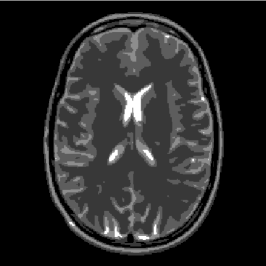

The cases () and () with and are usually called the synthesis formulation and expect the vector to be sparse. However, it is observed in many applications, that the vector is only transform sparse, i.e. sparse after an application of a suitable transform or often even only compressible, i.e. very few entries are large and the rest is small in modulus but not necessarily zero. For example, most natural images are compressible with respect to multiscale systems such as wavelets [16], curvelets [5] or shearlets [31]. More precisely, the transform coefficients decay to zero with a certain rate as the scales increase, see Figure 2. The transform sparse model is for instance used in magnetic resonance imaging (MRI) where the sparsity of medical images with respect to a wavelet transform is utilized cf. [39].

As already mentioned in the introduction, one of the applications of the analysis-based -minimization problem is magnetic resonance imaging where the sampling process is modeled by taking samples of the Fourier transform of the signal. The minimization problem for this application is

where is the shearlet transform and is the undersampled Fourier transform restricted onto a certain subset of frequencies. Typical choices for the set of measured frequencies are samples that lie on continuous trajectories such as horizontal lines, spirals, radial lines etc. For our numerical experiments we have chosen a radial sampling mask consisting of 30 radial lines, see Figure 3 below.